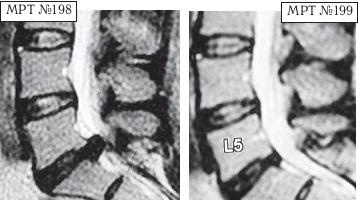

Пример № 4.

На МРТ № 198 наблюдается состояние поясничного отдела позвоночника: секвестрированная грыжа межпозвонкового диска в сегменте LV—SI абсолютный стеноз спинномозгового канала.

На МРТ №199 — состояние поясничного отдела позвоночника после лечения методом вертеброревитологии.